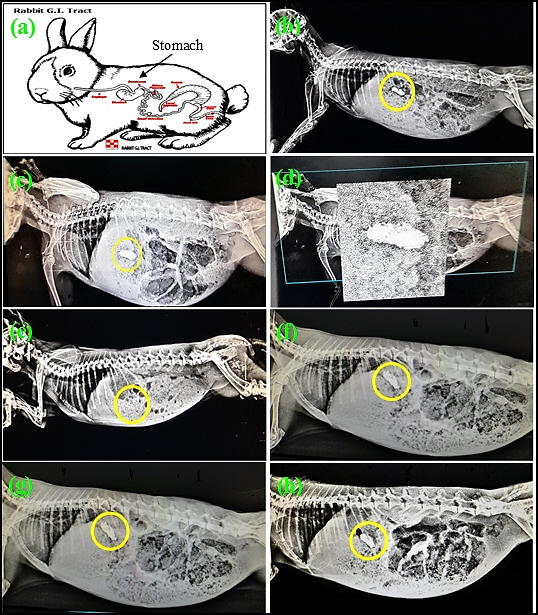

The X-ray imaging of oral capsules coating floating Famotidine/BaSO4 microspheres; Famotidine-Alginate, and Famotidine-GMO-Alginate microspheres after different times (0-12 h) were shown (fig. 9). Capsules containing Famotidine-Alginate, and Famotidine-GMO-Alginate microspheres were detected by X-ray at 5 min post administration fig. (7b, candd). After 3 h, capsules containing Famotidine-GMO-Alginate microspheres can be detected by X-ray, while capsules containing Famotidine-Alginate microspheres were not detected (fig. 7e,f), indicating low floating properties of Famotidine-Alginate microspheres. This is the reason why no further assessment of capsules loaded Famotidine-Alginate microspheres was performed after this time point [3 h]. At 6and12 h post-administration, capsules containing Famotidine-GMO-Alginate microspheres can be easily detected in the stomach by X-ray (fig. 7g,h), indicating superior gastric retention properties of Famotidine-GMO-Alginate microspheres.

Fig. 9: X-ray imaging of Capsules coating the Floating Famotidine microspheres; (a) Rabbit GIT diagram, (b) Famotidine-Alginate [5 min], (c) Famotidine-GMO-Alginate [5 min], (d) Famotidine-GMO-Alginate [5 min]5X magnification, (e) Famotidine-Alginate [3 h], (f) Famotidine-GMO-Alginate [3 h], (g) Famotidine-GMO-Alginate [6 h], and (h) Famotidine-GMO-Alginate [12 h]. BaSO4 was used as radiopaque contrast in all microspheres prepared